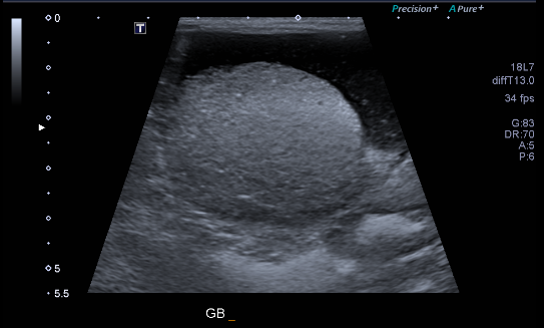

복부 초음파 검사를 실시하였고, 담낭의 확장과 점액종 양상이 확인되었습니다.